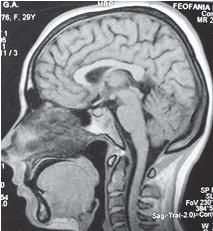

На МРТ № 50 наблюдается гиперлордоз шейного отдела позвоночника с плотным прилеганием спинного мозга к задним отделам спинномозгового канала и выраженными ликвородинамическими нарушениями (что хорошо видно на МРТ головного мозга).